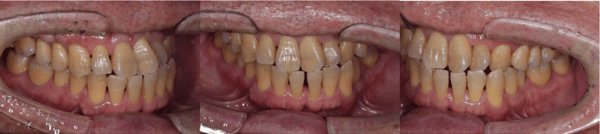

| 年齢 | 56歳・男性 |

|---|---|

| 主訴 | 定期検診 |

| 治療内容 | 歯周基本検査・歯石除去・着色除去・フッ素塗布 |

| 治療期間 | 60分 |

| 費用 | 保険診療約4,500円 (歯の本数や検査内容で料金が変動します。) (2023/12/25時点の価格) |

| リスク・副作用 | ・歯ぐきの炎症がある場合は歯石除去中に出血を伴う可能性があります。 ・処置後に歯がしみることがあります。 ・歯ぐきの炎症が軽減すると歯ぐきが引き締まり、歯が長く見えることがあります。 ・定期検診は予防の一環であり、検診の来院で必ず虫歯や歯周病にならない訳ではありません。 |

| 担当者所見 | ブラッシング指導後、歯石除去を行い定期検診へ移行 矯正治療を行う予定 |

| 特記事項 | 交叉咬合・かみ合わせが強い |

| 担当者所見 | 初診時は歯石が全顎的に付着しており、歯石除去時は出血もありました。特に下の前歯は歯と歯の間を埋めるように多量の歯石が付着していました。ブラッシング指導も行い、定期検診へと移行しました。 定期検診時は全体的な清掃状態も良好で、ご自身も歯ブラシを頑張っているとおっしゃっていました。矯正治療開始後も綺麗で健康な口腔内を維持する為、定期検診を継続的に行っていく予定です。 |